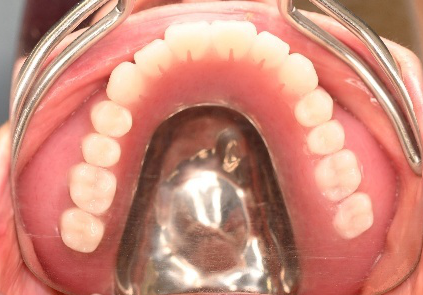

After

【義歯を装着したところ】

【義歯を外したところ】

【マグネット式総入れ歯】

緑丸は組み込まれたマグネット